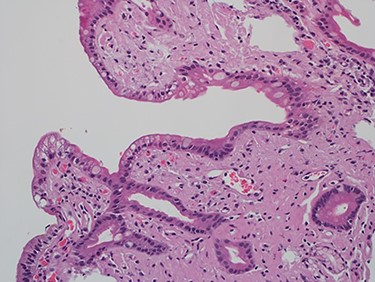

As work up for his abdominal pain and anemia he underwent gastroscopy on 29 October 2020 that revealed congested and nodular gastric mucosa (mass-like) and at lesser extend in the first and second part of duodenum (Figs 1 and 2). Biopsies were taken from the gastric lesion and duodenum. Histopathological findings from gastric mass and duodenum showed marked stromal hyalinosis, which appeared as a cellular pink material on H&E stain (Figs 3 and 5). Congo red stain (amyloid stain) showed apple green birefringence under polarized light on both gastric and duodenal biopsies (Figs 4 and 6).

High power of duodenal biopsy showing stromal hyalinosis (H&E x 20).